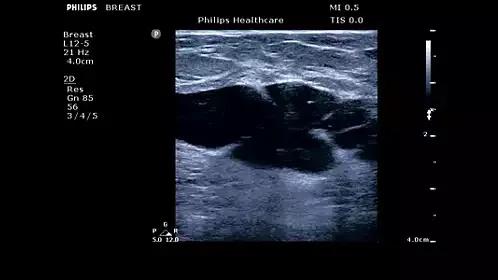

Elasto应变弹性成像,ClearVue 850利用不同组织间弹性系数不同,在受到外力压迫后组织发生变形的程度不同,借图像色彩反映组织的硬度。对于乳腺、甲状腺等器官的肿块判定,弥补了常规超声的不足,能够更准确地显示并定位病变,并可对肿块的应变范围进行测定及分析,帮助医生判定肿块性质。

ClearVue 850支持临床全方面应用,包括腹部、产科/妇科、血管、心脏、小器官、肌肉骨骼、泌尿、儿科、运动负荷超声心动图、IMT、乳房弹性成像和TCD等;革新型的Active Array技术,为您提供令人惊叹的高清晰度和精细分辨率的2D、血流及3D/4D图像。